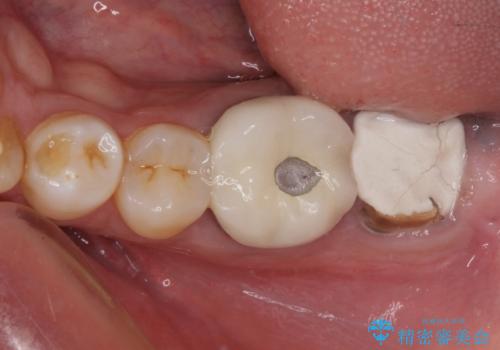

- 近医にて奥歯の抜歯が必要と言われたとのことで来院された患者様です。

診査の結果、歯が破折しており、抜歯が必要な状態でした。

最後方歯であるため、入れ歯かインプラントかどちらかの補綴治療を行うこととなりますが、ご希望によりインプラント補綴治療を行うこととしました。